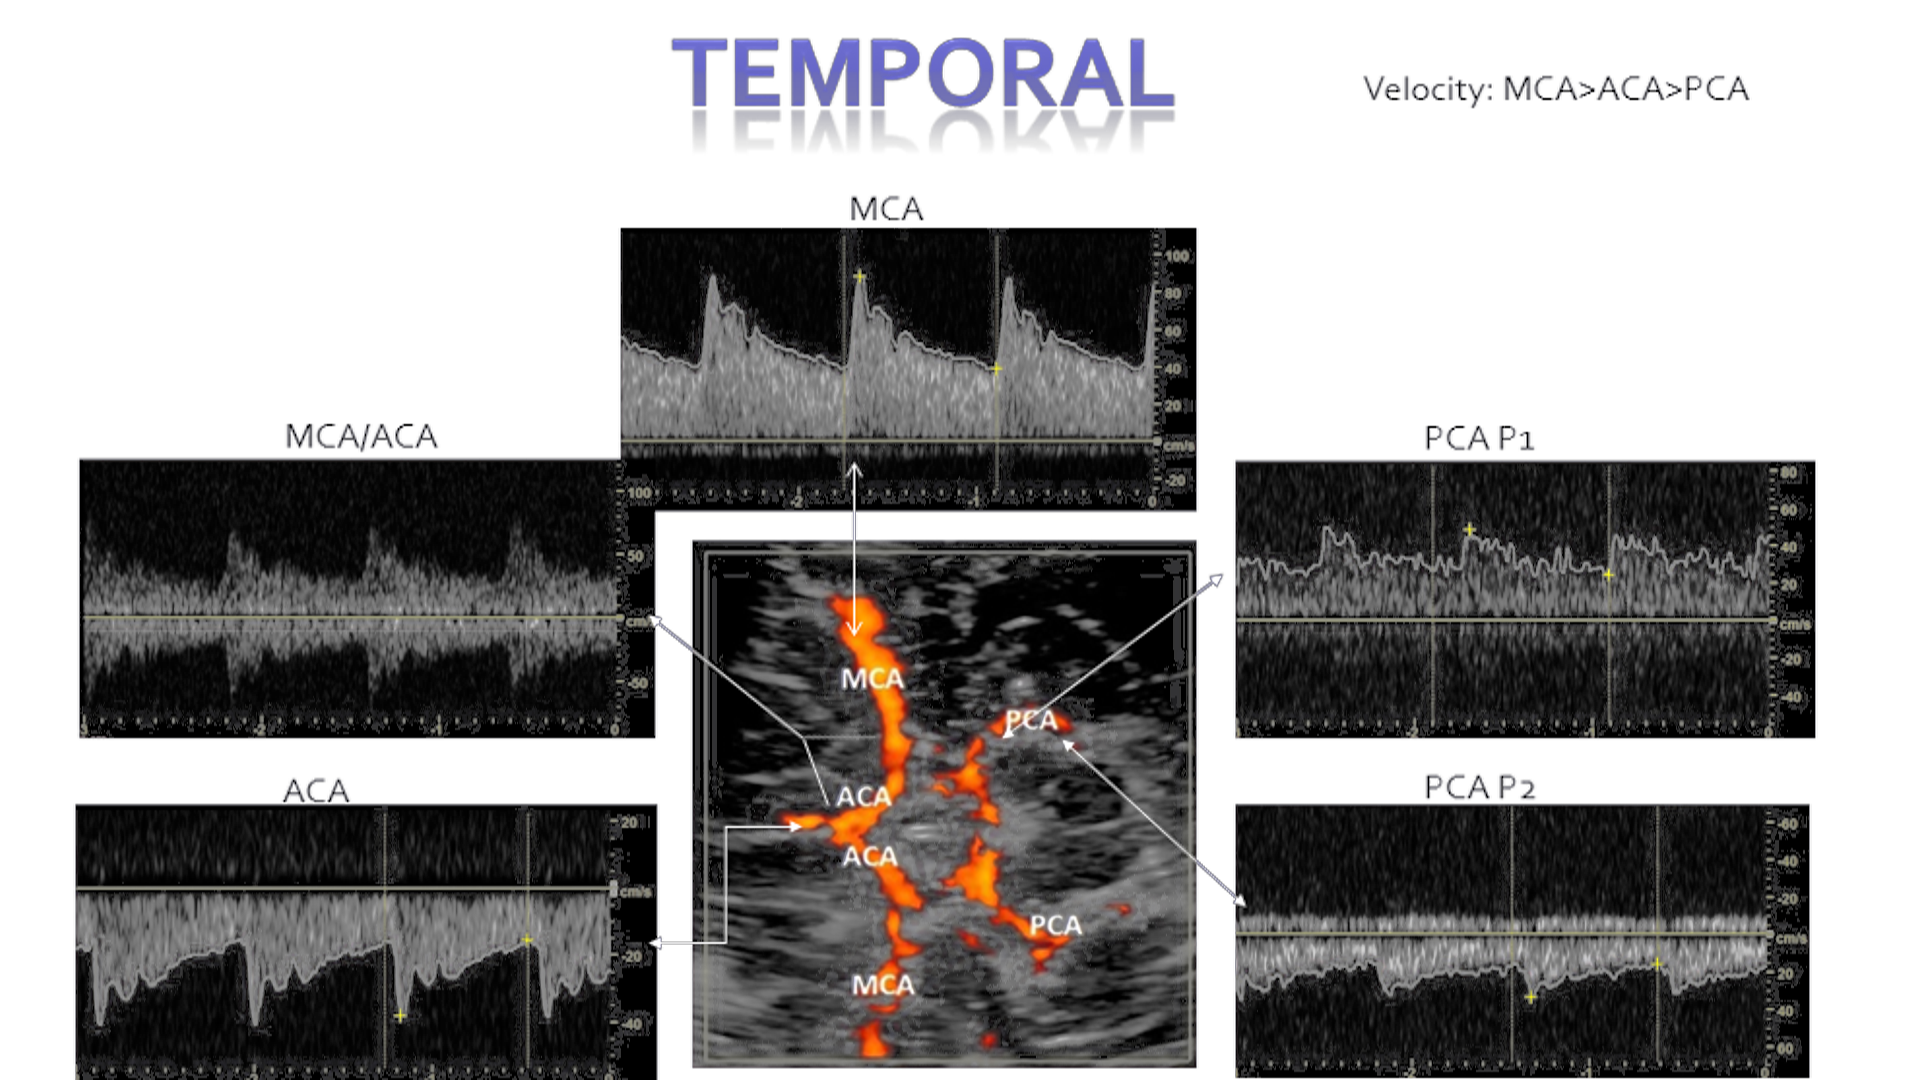

Temporal

In the temporal window you will scan the MCA, ACA and PCA advancing 2mm from distal to proximal in the MCA. Using a zero degree angle and a moderate sized gate. Flow directions are as follows. In the temporal window angling down you will be able to insonate the terminal ICA

MCA – Above baseline (typically highest in velocity)

ACA – Below baseline

PCA – Bi-directional (lowest in velocity of the 3 vessels)